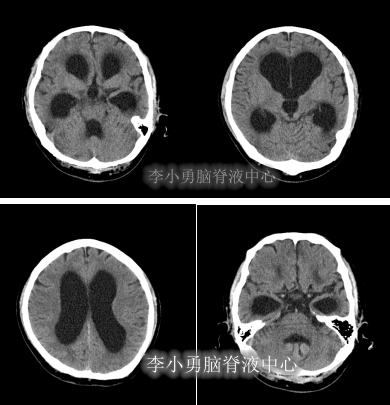

脑室外引流术后5天即2011年6月25日,查头部CT颅内仍有出血(图-4)。

图-4:2011年6月25日头部CT

拔除脑室外引流术后1天即2011年6月29日,头部CT示颅内出血基本消失(图-5),给予腰大池引流术。

图-5:2011年6月29日头部CT